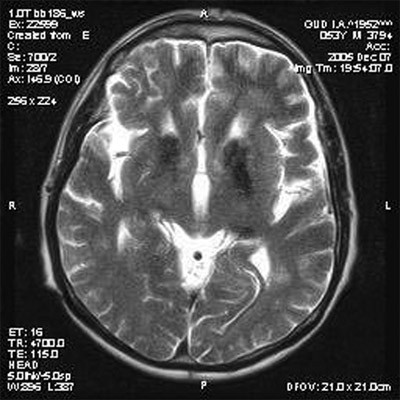

Специальные исследования

Для подтверждения диагноза Галлервордена-Шпатца и исключения других заболеваний проводятся специальные исследования, такие как:

- Нейрофизиологические исследования. Они включают в себя электромиографию (ЭМГ), электроэнцефалографию (ЭЭГ) и другие методы, которые позволяют оценить работу мышц, нервной и электрической активности мозга. Эти исследования могут помочь выявить нарушения в работе нервной системы и подтвердить диагноз.

Все эти исследования в комплексе помогают определить диагноз Галлервордена-Шпатца и оценить степень его проявления у пациента, что в свою очередь позволяет разработать индивидуальный план лечения и прогнозировать дальнейший ход заболевания.